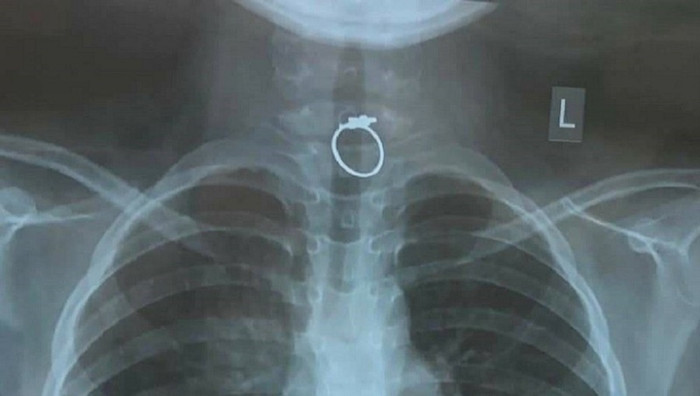

Phim chụp Xquang chiếc nhẫn mắc kẹt trong thực quản của bé gái. Ảnh: Pháp luật Việt Nam

Qua chụp phim cũng như là khám cấp cứu, các bác sĩ phát hiện một chiếc nhẫn kim loại đang kẹt ở vị trí 1/3 phía trên thực quản, ghim chặt vào niêm mạc.